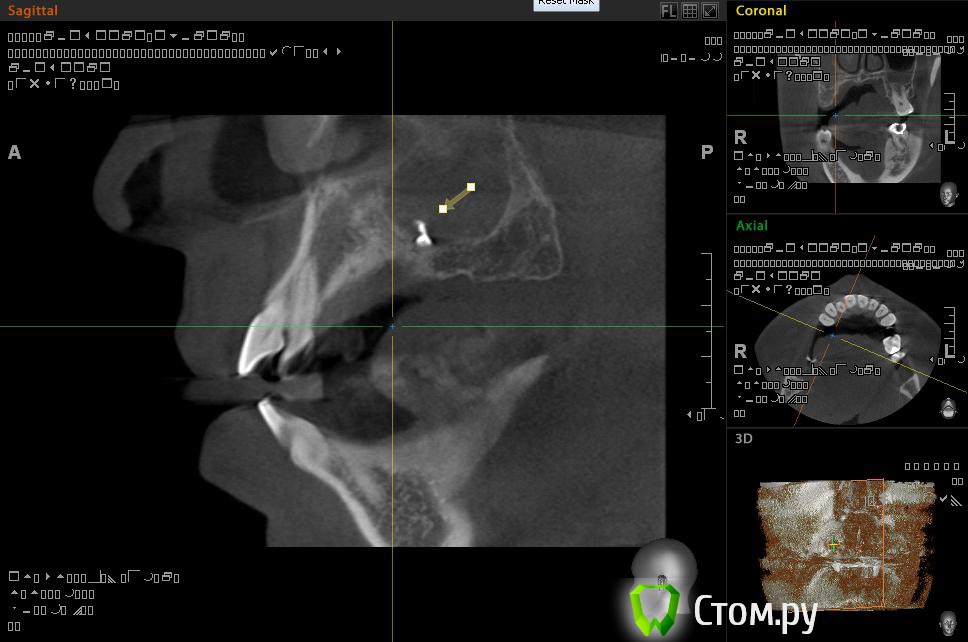

Евений Опубликовано 22 ноября, 2013 Поделиться Опубликовано 22 ноября, 2013 (изменено) Здравствуйте!В 2011 году делал КТ. Заполнена тотально правая пазуха, у медиальной стенки инородное тело овоидной формы, в центре которого объект металлической плотности, мелкие объекты на нижней стенке пазухи. Полипы у носового хода.После этого была радикальная гайморотомия на правой пазухе. Обнаружили застарелый хронический процесс, творожистые массы, поставили холеастому. Гистология операционного материала показала наличие грибка.По своей инициативе сделал 3d-томографию на picasso trio.Рентгенолог сказал про уровень в пазухе и инородное тело.КТ делал во время простуды, был насморк.Сходил на консультацию к профессору, который меня оперировал. Внимательно осмотрев носовую полость он ничего не нашел. Про КТ сказал, что это могут быть корни зубов. Пломбировочный материал отрицает, как и перед операцией. На данный момент - простуда, и оперированную пазуху закладывало больше чем здоровую. Выделения прозрачные, потом желтые и оранжевые.. Из минусов, как и раньше стекает слизь по задней стенке. Вопрос такого плана: Что за загогулины в правой оперированной пазухе? Целесообразно ли делать микрогайморотомию после радикальной, или если будут делать то опять радикальную?Спрашиваю потому, что уже не знаю к кому обращаться у нас в Архангельске. Вроде, операция радикальная была под контролем эндоскопа, уж должны были всё проверить и достать. Делал операцию академик, светило медицины в области хирургической стоматологии и онкологии.И еще - а стоит ли вообще делать вторую операцию? Возможно вред от вмешательства и наркоза перетянет пользу операции. Спасибо!ССЫЛКА НА РЕЗУЛЬТАТЫ ПИКАССО ТРИО http://dfiles.ru/files/qc62dn476 Изменено 22 ноября, 2013 пользователем Евений Ссылка на комментарий

АнтонТЛТ Опубликовано 22 ноября, 2013 Поделиться Опубликовано 22 ноября, 2013 Найдите хорошего ЛОРа, который нормально уберет остатки пломбировочного материала 2 Ссылка на комментарий